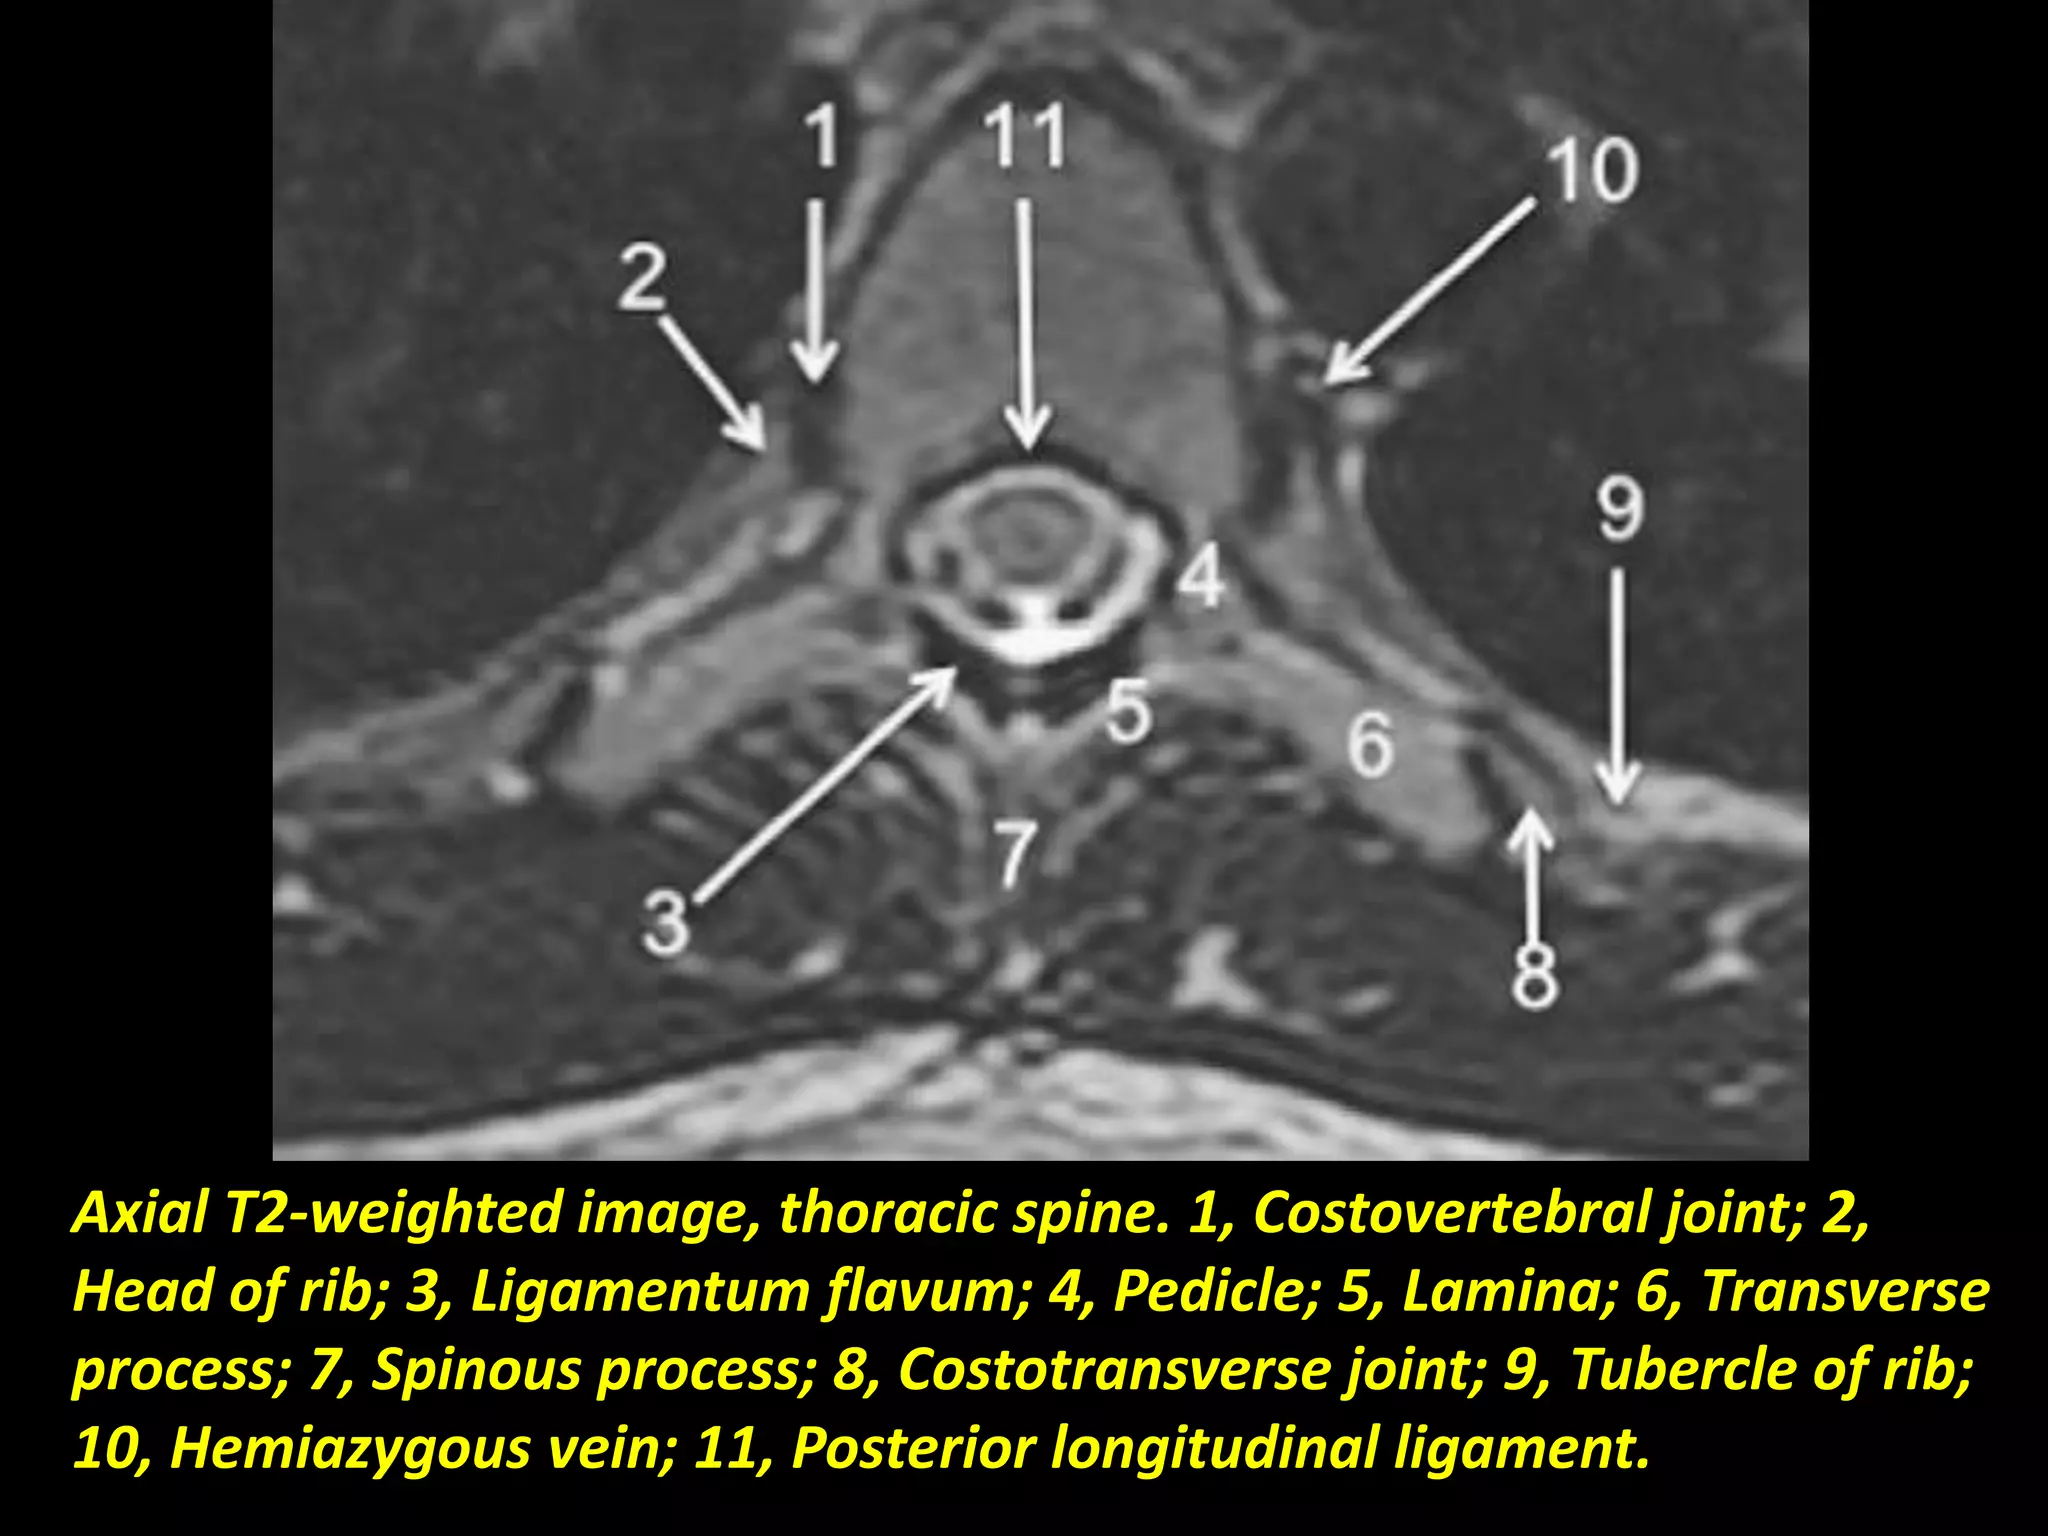

Axial T2-weighted image, thoracic spine. 1, Costovertebral joint; 2,

Head of rib; 3, Ligamentum flavum; 4, Pedicle; 5, Lamina; 6, Transverse

process; 7, Spinous process; 8, Costotransverse joint; 9, Tubercle of rib;

10, Hemiazygous vein; 11, Posterior longitudinal ligament.

Axial T2-weighted image,thoracic spine. 1, Costovertebral joint; 2, Head of rib; 3, Ligamentum flavum; 4, Pedicle; 5, Lamina; 6, Transverse process; 7, Spinous process; 8, Costotransverse joint; 9, Tubercle of rib; 10, Hemiazygous vein; 11, Posterior longitudinal ligament.